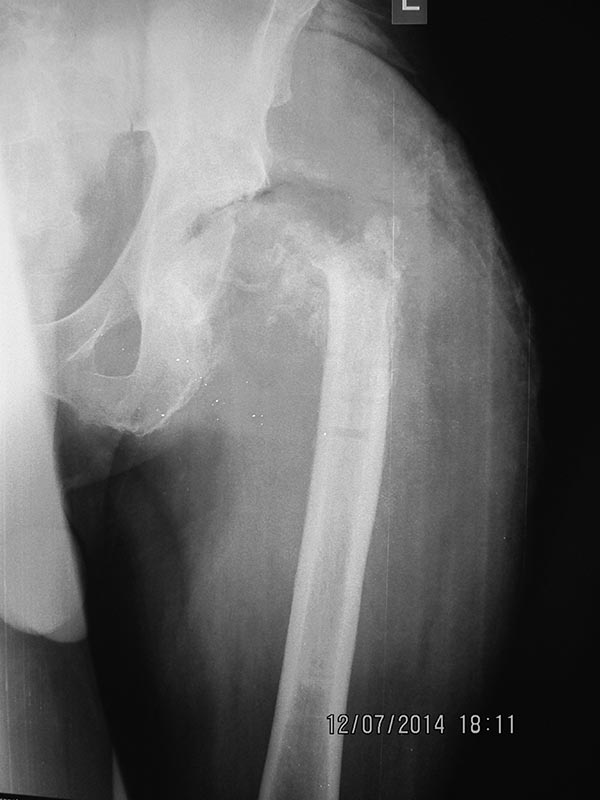

Был схожий случай. Нагноение после ревизионного эндопротезирования тазобедренного сустава. Каждая некроектомия формировала все большую остаточную полость, мощные рубцовые стенки которой не давали ей сомкнуться. Ушивание раны с АПОД только усугубляет ситуацию, так как способствует этому. Проблему решили заполнением полости латеральной порцией четырехглавой мышцы бедра на питающей ножке (см фото, что нашел в архиве). На момент операции размеры полости были таковы, что всей, гипотрофированной к тому времени, мышцы просто не хватило для тампонады. Сформировался свищ, который закрылся через несколько недель.

На Вашем месте я бы выполнил некроектомию + бусы + NPWT. После купирования гнойного процесса тампонировать мышцей.

судя по картинке - особых надежд на NPWT я бы не возлагал. Я бы использовал ротационный лоскут из прямой мышцы живота, коллеги из Ярославля, судя по докладам, успешно его применяют. К сожалению, опыта таких лоскутов на этом сегменте не имею. На мой взгляд, спейсер с ваком сами по себе при такой ране "не сработают"

Здравствуйте, Гурген. Радикальная хирургическая обработка мягких тканей и костей образующих т/б сустав (обработка вертлужной впадины фрезами и бедренной кости до "кровянной росы", обработка канала бедренной кости развертками), санация, тампонировать канал и рану салфетками с Лавасептом на время замены белья. Выделить латеральную головку квадрицепса на питающей ножки, ротировать лоскут дистальной частью в т/б сустав. При невозможности ушивания раны, дефект можно закрыть вакуумной повязкой, ждать грануляций, после кожная пластика. Неудобство для пациента - тазобедренная гипсовая повязка с окном. Желаю удачи!